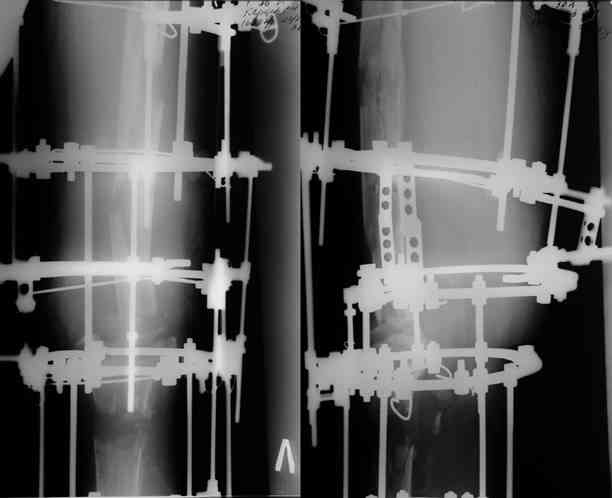

Этот стиль мне полностью приемлем и понятен. Наверно я бы поступил также. Но статистика упрямая вещь. Сколько у тебя или у другого врача опыта по замещению дефектов бедра? У меня за 25 лет работы 3, и еще около 15 случаев удлинения бедра. Случай у тебя очень сложный. Если Вы выбираете Илизаровскую методику то надо на в/з хорошую дугу, не менее 4-5 спиц с напайками.Стержни хороши когда кость не измучена и на 2-4 месяца. Здесь аппарат на 6-8 месяцев. Если есть желание я только за, и

Прикрепляю пример замещения дефекта бедра 20 см, после резекции по поводу опухоли, эндопротеза Сиваша, вялотекущего остеомиелита со свищами в течении 3 лет. Получилось хорошо и всего за 6 месяцев в аппарате. Колена не было. У Вас случай сложнее. Это было в 1998г. Я работал в ЦИТО и у меня было 4 больных, я занимался им с утра до ночи. Сейчас 60 больных и операций в нашем отделении 25-30 в неделю.Если могу чем помочь - нет проблем.